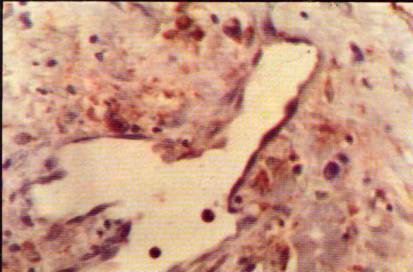

Foto

17: Importante concentración de macrófagos en el borde tumoral (M); arriba

tejido

18: Sector del borde tumoral a mayor aumento, macrófagos (M) Anti-macrófagos,

Foto 19: Macrófagos rodeando estructura vascular de paredes gruesas <Anti-macrófagos Hematoxilina> 300 X.

20: Estructura vascular de paredes delgadas, endoteliales rodeada por macrófagos

21: Macrófagos intratumorales que rodean elementos celulares multinucleados,

Foto 22: Macrófagos en área necrótica. <Anti-macrófagos, H> 300 X.

23: Elemento celular marcadamente atípico rodeado por macrófagos (M) con

signos

Foto 24: Inmunomarcación para células "T" mostrando intensa positividad en los márgenes tumorales <UCHL-1, H> 300 X.

25: Elementos linfoides "B" en las adyacencias y en la pared de una

arteriola

26: Plasmocitos intensamente secretores marcados para cadenas Lambda

<AntiLambda, Hematoxilina> 300 X.

Es interesante destacar que en sectores con escasa necrosis se ven

mayor número que en las áreas más necróticas tanto centrales como adyacentes

al borde, como si en lugar de ser atraídos por la necrosis tuvieran relación

causal con ella (foto 21 comparada con 22).

Por otra parte en el límite tumoral se destacan algunos elementos

celulares marcadamente atípicos totalmente rodeados por macrófagos, notándose citólisis inicial en los elementos

neoplásicos (foto 23).

La marcación para células "T' mostró intensa positividad con

ubicación peritumoral en barrera limitante y en sectores perivasculares (foto

24), asimismo se observó positividad intratumoral escasa.